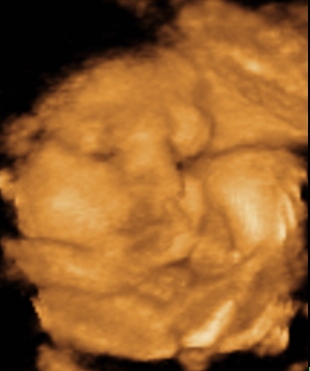

Nimród a 31. héten:

Kép